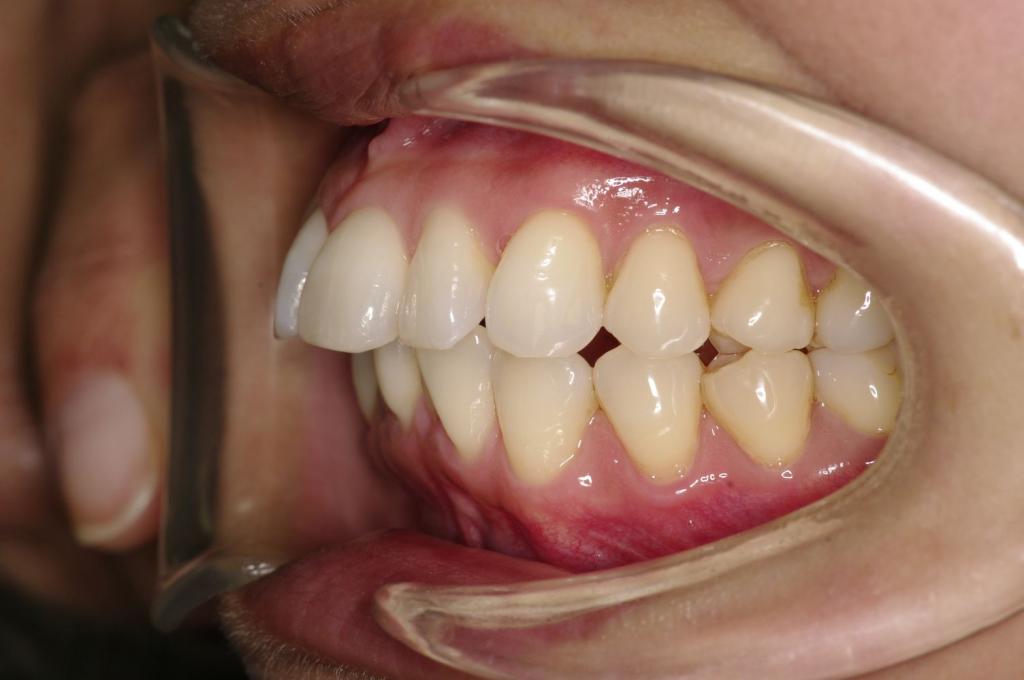

前歯、出っ歯・開咬の矯正治療

(治療期間、治療前後写真、治療方法、費用)WORKS